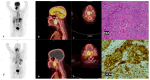

Materials and methods: In this prospective cross-sectional study, twenty-three (23) patients aged 52.9 ± 10.4 (19.6), 17 males and 6 females with primarily diagnosed (n = 17) or pre-treated (n = 6) SCC of the oral cavity (OCSCC, n = 11), oropharynx (OPSCC, n = 9), nasopharynx (NPSCC, n = 2) and unknown primary (n = 1) underwent imaging with [68Ga]Ga-Pentixafor-PET/CT. In 16/23 patients 2-[18F]fluoro-2-deoxy-D-glucose ([18F]F-FDG) served as a standard reference. All lesions were visually rated using a 5-point Likert scale. For both tracers, maximum standardized uptake values (SUVmax) and the total lesion uptake (TLU) were recorded and compared using the Wilcox-signed rank test. In addition, the tumor-to-background ratios were derived using the liver (TLR), spleen (TSR), and posterior cervical muscles (TMR) as background. The relationships between the SUVs of the two tracers were assessed using the Spearman correlation. CXCR4 immunohistochemistry (IHC) staining was correlated with 68Ga-Pentixafor-PET/CT in 21/23 patients.

Results: Ninety-one percent (21/23) of tumors were visually detected on [68Ga]Ga-Pentixafor; however, [68Ga]Ga-Pentixafor was less intense compared with [18F]F-FDG-PET. Quantitative analysis showed higher [18F]F-FDG SUVmax in comparison with [68Ga]Ga-Pentixafor (16 ± 6.7 vs. 5.8 ± 2.6 g/mL, p = 0.011) and SUVmean (9.3 ± 4.1 vs. 3± 1.6 g/mL, p < 0.001) and TBR 4.9 ± 2.3 vs. 2.36 ± 1.4 p = 0.014. Nasopharyngeal cancer demonstrated more intense tracer accumulation than oropharyngeal and oral cavity malignancies. CXCR4 IHC staining was positive in 15/21 patients, and there was a statistically significant correlation between IHC staining and [68Ga]Ga-Pentixafor SUVmean r = 0.5 p = 0.027, and performance status r = 0.83 p = 0.0104.

Conclusions: In conclusion, although [68Ga]Ga-Pentixafor cannot replace [18F]F-FDG as a diagnostic tool because of its lower avidity, the correlation between CXCR4 targeted 68Ga-Pentixafor PET imaging and CXCR4 IHC staining indicates the potential of 68Ga-Pentixafor as an effective tool for selecting patients who may benefit from therapies targeting CXCR4. In addition, [68Ga]Ga-Pentixafor has no physiological brown fat uptake, which often obscures cervical lesions on [18F]F-FDG PET/CT imaging.